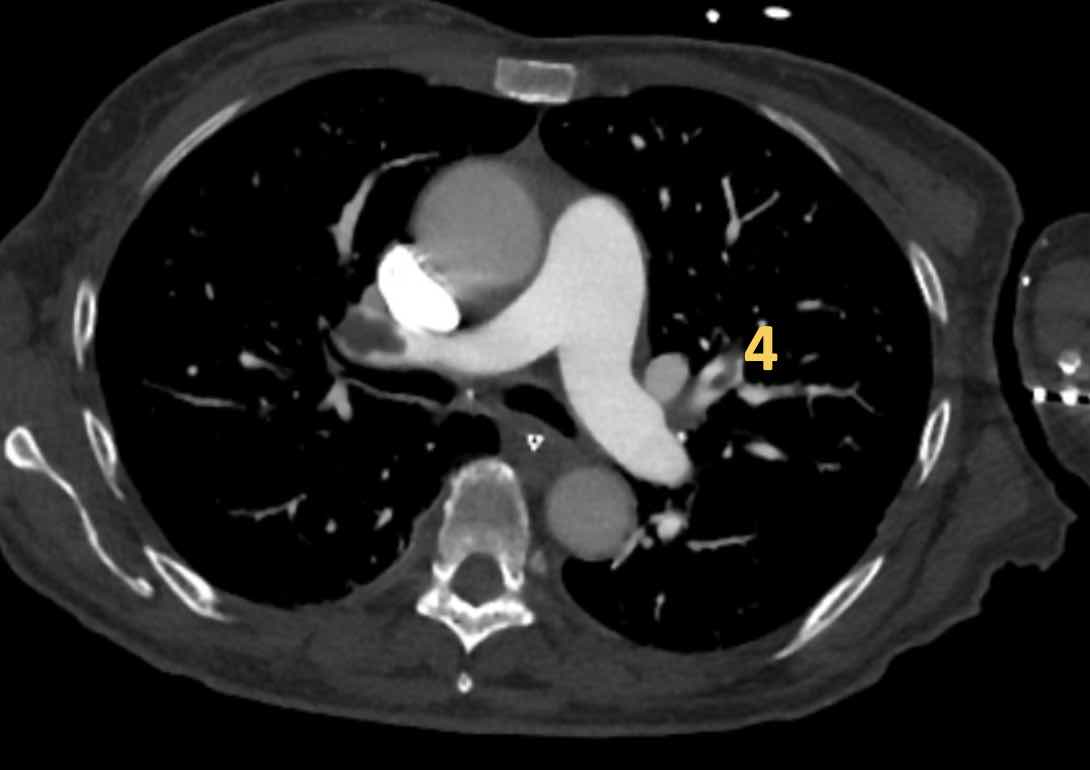

Có huyết khối phân thùy tắc nghẽn cấp tính trên nền mạn tính ở phân thùy trước của thùy trên phổi trái

(mũi tên đen).

Tắc nghẽn phân thùy có sẵn ở các nhánh đáy với hẹp đột ngột của các mạch máu ngoại vi (mũi tên xanh).

Đây là các hình ảnh của bệnh nhân nam 53 tuổi

mắc tăng áp động mạch phổi.